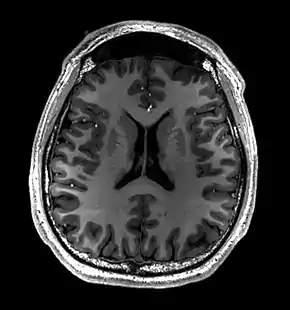

- T1-weighted (T1W) images: Cerebrospinal fluid is dark. T1-weighted images are useful for visualizing normal anatomy.

- T2-weighted (T2W) images: CSF is light, but fat (and thus white matter) is darker than with T1. T2-weighted images are useful for visualizing pathology.[26]